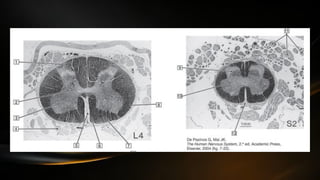

• Encontramos 3 tipos diferentes de neuronas: eferentes, aferentes e

intermedias

• Neuronas eferentes envían su axón fuera del SNC, pueden ser

motoneuronas o vegetativas

• Las motoneuronas están en el asta anterior y las vegetativas en la

región intermedia

• Las neuronas aferentes son de naturaleza sensitiva e informativa

ocupan el asta posterior de la medula

• Las interneuronas se encuentran por toda la medula dispersas

• La sustancia blanca es un manto de axones que es su mayoría estan

mielinizados

• La sustancia blanca esta dividida por las astas y las fibras radiculares

de las raíces espinales en tres regiones:

• Cordones posteriores: están entre la línea media y el asta posterior con sus

fibras radiculares

• Cordones anteriores: situado entre la fisura mediana anterior y el asta

anterior

• Cordones lateral se dispone lateralmente a la sustancia gris entre las fibras

radiculares anteriores y posteriores

• Hay una variación de la forma de la sustancia gris conforme se

desciende en la medula espinal (a nivel de los miembros la sustancia

gris se torna mas gruesa)